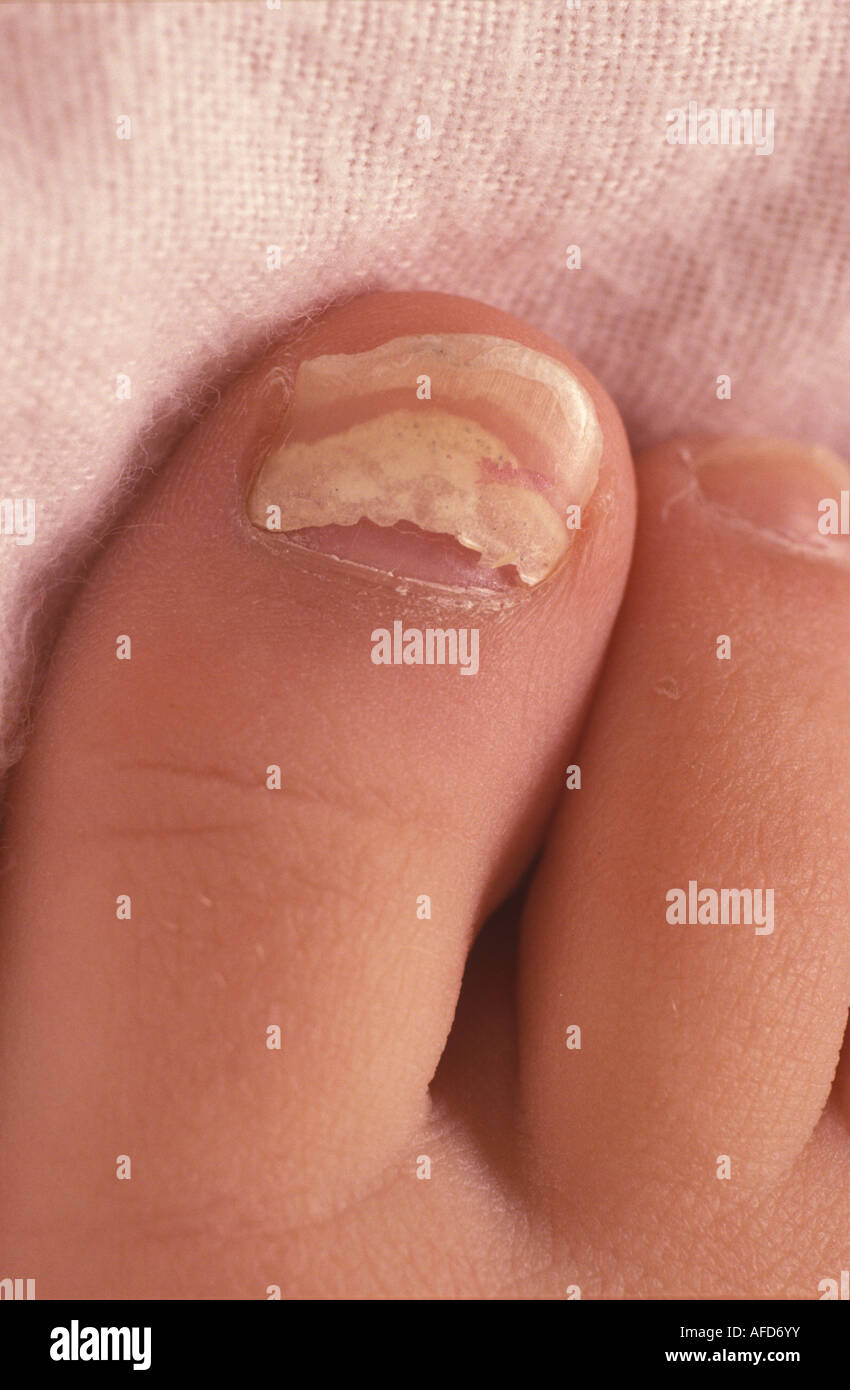

RMBP4KXE–Pilzartige Infektion. Blick auf die gebrochen, verfärbte und schlecht wachsenden Fußnägel mit Pilz (Tinea Unguium) infiziert

RMBP4KXJ–Pilzartige Infektion. Blick auf die gebrochen, verfärbte und schlecht wachsenden Fußnägel mit Pilz (Tinea Unguium) infiziert

RMBP4KXY–Pilzartige Infektion. Blick auf die gebrochen, verfärbte und schlecht wachsenden Fußnägel mit Pilz (Tinea Unguium) infiziert